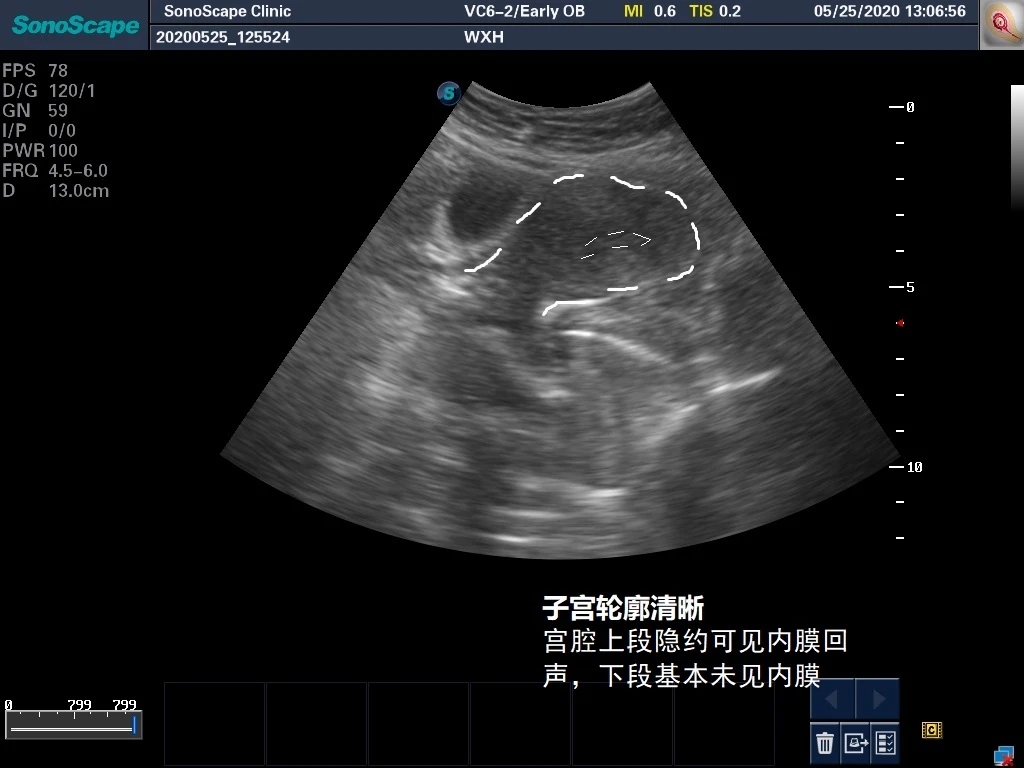

在上面这个图片中,我们可以大约看到子宫的轮廓以及微弱的内膜回声,标注呈现如下图: